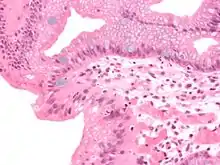

| Micrograph of a gastro-esophageal junction with pancreatic acinar metaplasia. The esophageal mucosa (stratified squamous epithelium) is seen on the right. The gastric mucosa (simple columnar epithelium) is seen on the left. The metaplastic epithelium is at the junction (center of image) and has an intensely eosinophilic (bright pink) cytoplasm. H&E stain. |